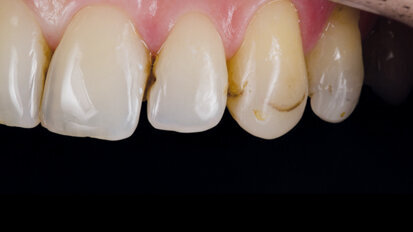

Nový úsměv za jeden den

Čt. 28. května 2020